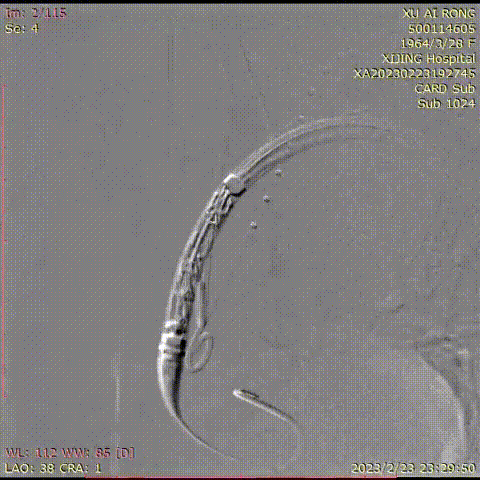

主体支架释放后造影

主体支架窗口

与分支动脉开口存在偏差

利用自适应性成功超选左颈总动脉,并置入分支支架

利用自适应性成功超选无名动脉,并置入分支支架

利用自适应性成功超选左锁骨下动脉,

并置入分支支架

术后造影